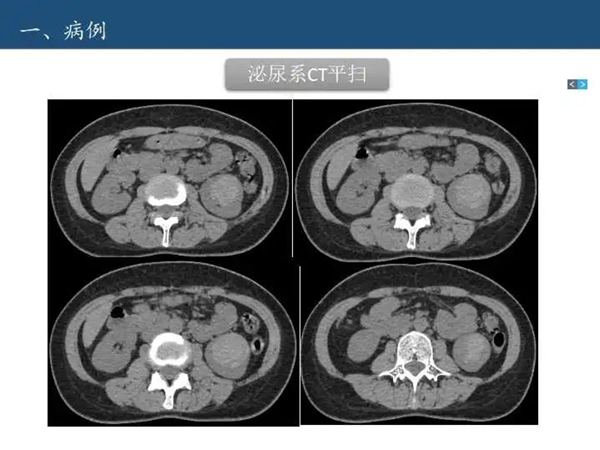

病例讨论—肾脏囊性病变Bosniak分级